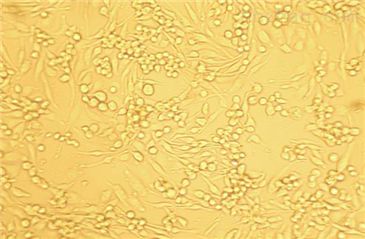

| 细胞名称 | Daudi人淋巴瘤细胞 |

| 细胞形态 | 悬浮;淋巴母细胞样 |

| 培养条件 | RPMI-1640 +10% FBS;37℃,5% CO2 |